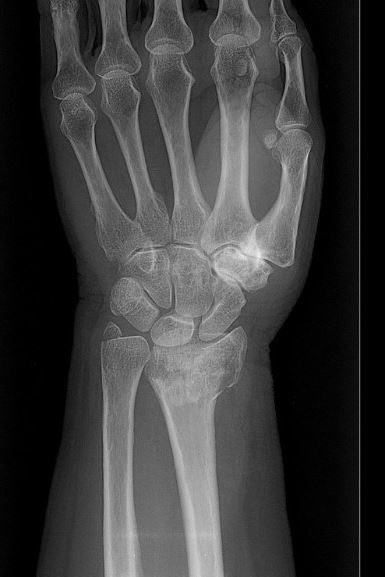

Gebroken linker pols

De meest voorkomende fractuur is de distale fractuur van de radius. Het is belangrijk dat de arts weet welk type fractuur u hebt. Het type bepaalt namelijk de behandeling.

- Bij onstabiele verplaatste fracturen is de stand van de pols vaak anders in vergelijking met de andere hand.